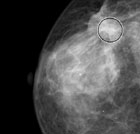

Porzione di una mammografia in cui Galileo ha cerchiato un'opacità

Galileo, l’occhio informatico per la prevenzione dei tumori

La computer aided detection fa un passo avanti con un software che coadiuva il medico nell’esame dei referti mammografici. Il programma, realizzato dall’Università di Bologna, è il primo che, utilizzando il machine learning, impara a riconoscere le anomalie direttamente dalle mammografie digitali  che gli vengono sottoposte.